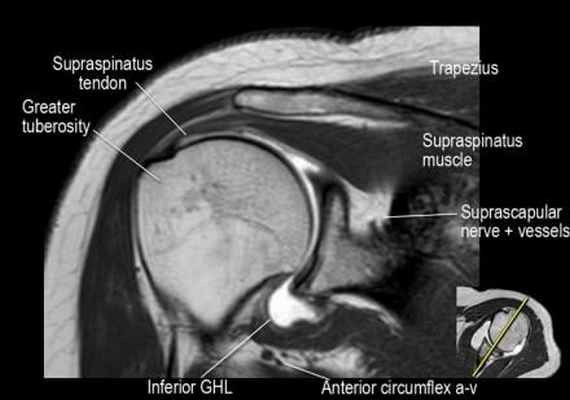

Нормальная корональная анатомия плечевого сустава и контрольный список

- обратите внимание на клюво-ключичную связку (coracoclavicular ligament) и короткую головку двуглавой мышцы (short head of the biceps).

- обратите внимание на клювоакромиальную связку (coracoacromial ligament).

- -

- обратите внимание на надлопаточный нерв и сосуды (suprascapular nerve and vessels)

- поищите импинджмент надостной мышцы за счет остеофитов в акромиально ключичном суставе или из-за утолщения клювовидноакромиальной связки.

- изучите верхний комплекс двуглавой мышцы и суставной губы, поищите подгубный карман илм SLAP-повреждение

- поищите скопление жидкости в подакромиальной сумке и повреждение сухожидия надостной мышцы

- поищите частичный разрыв сухожилия надостной мышцы в месте его прикрепления в виде кольцевидного повышения сигнала

- изучите область прикрепления нижней плече-лопаточной связки. Изучите нижний комплекс суставной губы и связок. Поищите HAGL-повреждение (humeral avulsion of the glenohumeral ligament).

- поищите повреждение сухожилия подостной мышцы

- обратите внимание на небольшое повреждение Хилл-Сакса